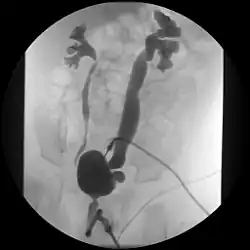

Klassifikation des Refluxes

Das International Reflux Study Committee hat 1985 eine allgemein gültige Schweregradeinteilung des vesikorenalen Refluxes erarbeitet:

- Grad I: Reflux in den Ureter, das Nierenbecken wird nicht erreicht

- Grad II: Der Reflux erreicht das Nierenbecken, das Kelchsystem ist nicht gestaut

- Grad III: Das Nierenbecken ist leicht dilatiert, das Kelchsystem ist unverändert oder leicht verplumpt

- Grad IV: Mäßige Dilatation des Nierenbeckens, die Fornices der Nierenkelche sind verplumpt, die Impressionen der Nierenpapillen noch sichtbar

- Grad V: Der Ureter ist stark dilatiert mit Knickbildung (Kinking), das Hohlraumsystem ist stark erweitert, die papillären Impressionen sind in der Mehrzahl nicht mehr sichtbar.